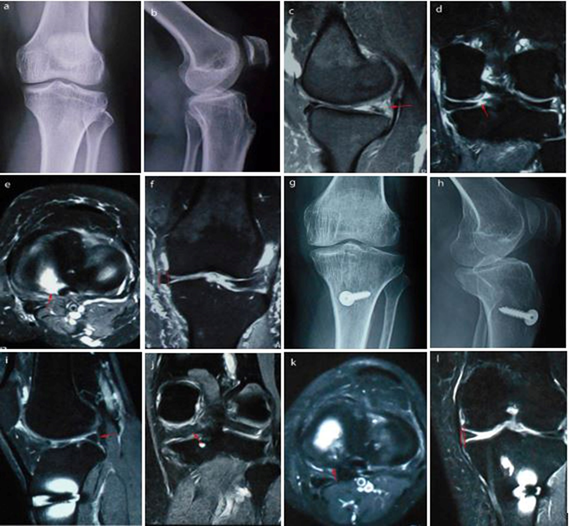

Out of 10 patients, 2 are male and 8 are female. The male: female ratio is 1:4. Mean age of the patient is 64 years (Range, 60 – 75 years). The mean follow-up period is 30 months (Range, 24-36 months). Mean BMI of the patients is 26.14 + 1.95 kg/m2 (Range, 22.5 – 29.2 kg/m2) (Table 1). No patients complain of pain, catching or giving way. No patient had joint line tenderness or effusion. The difference in mean preoperative and postoperative patient’s IKDC and Lysholm score are significant (Table 2). Follow-up MRI is performed in all the patients in which only 2 patients show complete meniscus root healing (Figure 2), 8 patients show partial meniscus root healing (Figure 3) and there was no case of repeat tear. Mean extrusion of meniscus decreases from 5.2 + 0.8 mm (Range, 4 -7 mm) preoperatively to 4.13 + 0.55 mm (Range, 3.5 - 5.2 mm) postoperatively, respectively.

Figure 3 Preoperative left knee.

a) Anteroposterior. b) Lateral radiographs. c) Preoperative MRI showing root tear (red arrow) in sagittal. d) Coronal. e) Axial. f) Meniscus extrusion (measured between two red vertical lines). g) Radiographs at 3 years follow up anteroposterior. h) Lateral view. i) MRI scans at 3 years follow up showing partial healing (red arrow) on sagittal view. j) Coronal view. k) Axial view. l) Coronal view showing decrease meniscus extrusion (measured between two red vertical lines)